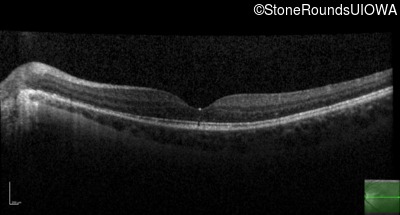

Optical Coherence Tomography - Left - 20/50

Exemplar / OCT Stack